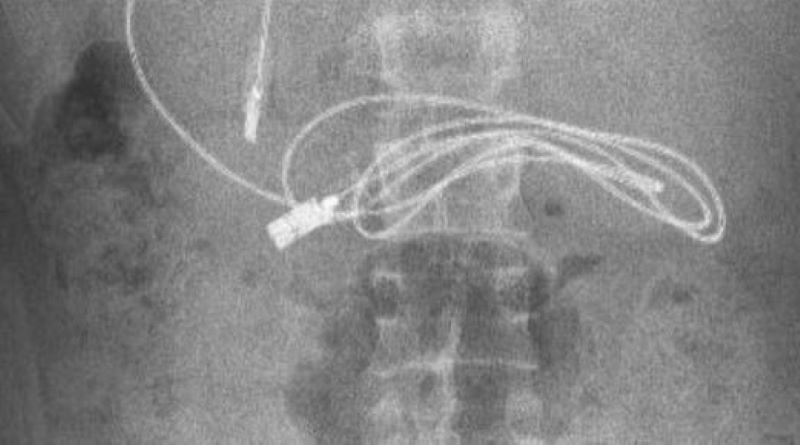

Brenda stomakut të një 15-vjeçari u gjet një kabllo të adapterit të telefonit.

Siç raportojnë mediat, kablloja ishte e gjatë një metër dhe se ishte e lidhur në nyje dhe kjo ua bëri mjekëve më të vështirë heqjen e tij.